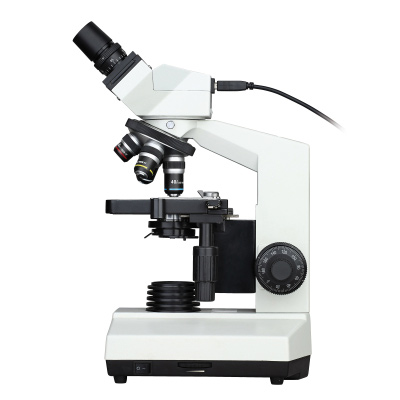

Binocular microscope